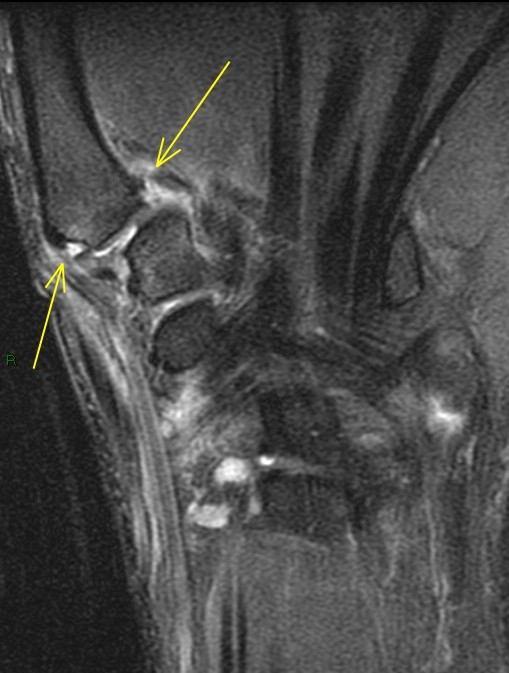

26 y/o crashed on a skateboard.

Patient has torn the deep anterior oblique ligament (beak), and sprained the superficial anterior oblique ligament, posterior oblique ligament and first intermetacarpal ligament. Also a sprain of the dorsoradial ligament. The joint has reduced but the patient related that he can slip it in and out easily. First images are from a dedicated thumb exam and the last image is from the wrist exam.

trapeziometacarpal dislocation